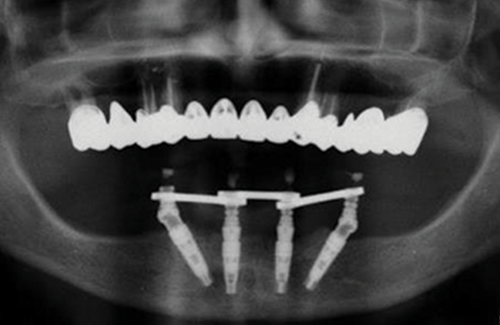

a. After screwing the titanium cylinders and taking an X-ray to ensure that everything is down, take the measuring tool from the Easy Bar kit and measure the distance between each titanium cylinder and elect the correct easy bar.